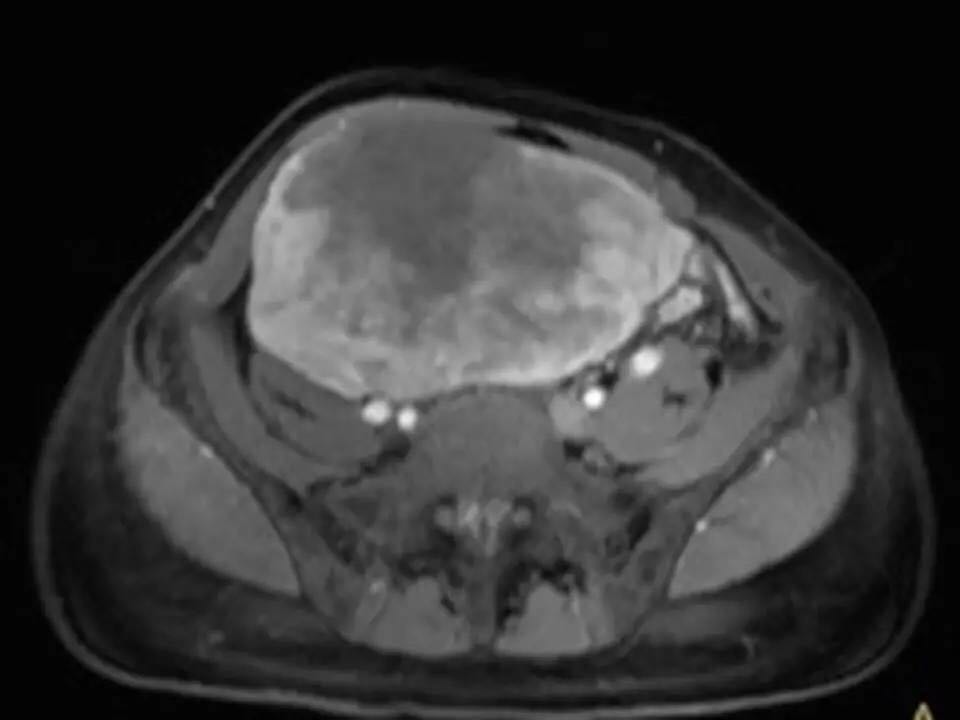

MRI表现,腹盆腔见不均质肿块,与肌肉相比为等低密度,强化不明显。T1WI信号均匀,T2WI高低混杂信号,增强后渐进性强化,病变各序列可见斑片状低信号区。 诊断,腹腔侵袭性纤维瘤病。

AF的影像学表现具有一定特征性。影像上表现为边界欠清的软组织肿块,钙化、出血少见,即便在较大的肿瘤中也看不到中央性坏死。病灶CT密度欠均匀,与邻近骨骼肌相近,强化不明显。T1WI信号基本均匀,明显或中度强化,典型强化方式呈渐进性。所有序列中都可以看到一定的低信号区,在病理上相对应的为病变内胶原纤维丰富的区域,此区域强化较轻。 侵袭性纤维瘤病虽然少见,但是平常工作中需要考虑到侵袭性纤维瘤病的诊断,尤其是中年女性腹腔的肿块。MRI为最佳的检查方法,可以显示一定的影像学特征。